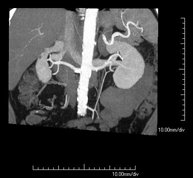

- Abdominal aorta CT angiography

A non-invasive diagnostic test that involves studying the abdominal aorta by obtaining high-definition anatomical images using CT (computed tomography) equipment and iodinated contrast. With the aid of workstations specialised for arterial studies, the image quality supports 2D and 3D reconstructions. It is indicated in patients with vascular disease (atherosclerosis), aortic aneurysms, abdominal pain of possible vascular origin, pre-surgical studies of lesions adjacent to the abdominal aorta as a vascular ‘map’, etc. Information obtained non-invasively is indispensable for patients requiring percutaneous or surgical processing. In patients who only require tracking of vascular lesions, this technique is the non-invasive technique of choice, together with MRI angiography.

- Renal artery CT angiography

A non-invasive diagnostic test that involves studying the renal arteries by obtaining high-definition anatomical images using CT (computed tomography) equipment and iodinated contrast. With the aid of workstations specialised for arterial studies, the image quality supports 2D and 3D reconstructions. This test is recommended, for example, in patients suffering from refractory hypertension that does not respond to processing, in patients with kidney damage in order to obtain a pre-surgical ‘vascular’ map, etc.

- Aortoiliac CT angiography

A non-invasive diagnostic test that involves examining the iliac arteries and abdominal aorta, obtaining high-definition anatomical images using CT (computed tomography) equipment and iodinated contrast dye. With the aid of workstations specialised for arterial studies, the image quality supports 2D and 3D reconstructions. This test is particularly recommended as a pre-surgical study (vascular map) prior to percutaneous or surgical interventions on the abdominal aorta, as a complementary study in patients with lower limb ischaemia, etc.